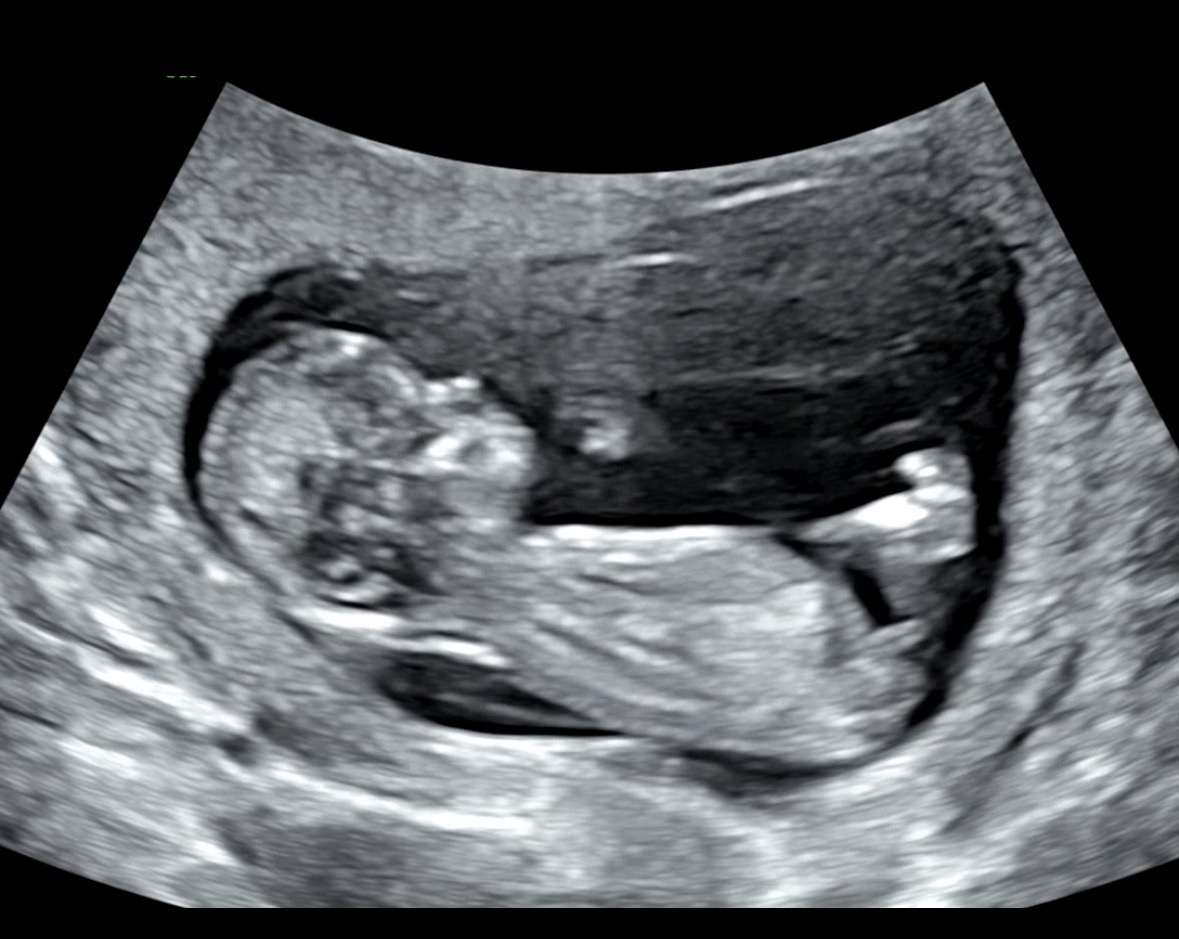

12주 3일 각도법 봐주세요오!!!!💜

보이실까욥 ㅠ 전혀 모르겠어요 ㅠㅠ 남아일까요 여아일까요?!

아들 같아요:)

아들 같아용

아들 한표요~

남아 한표용